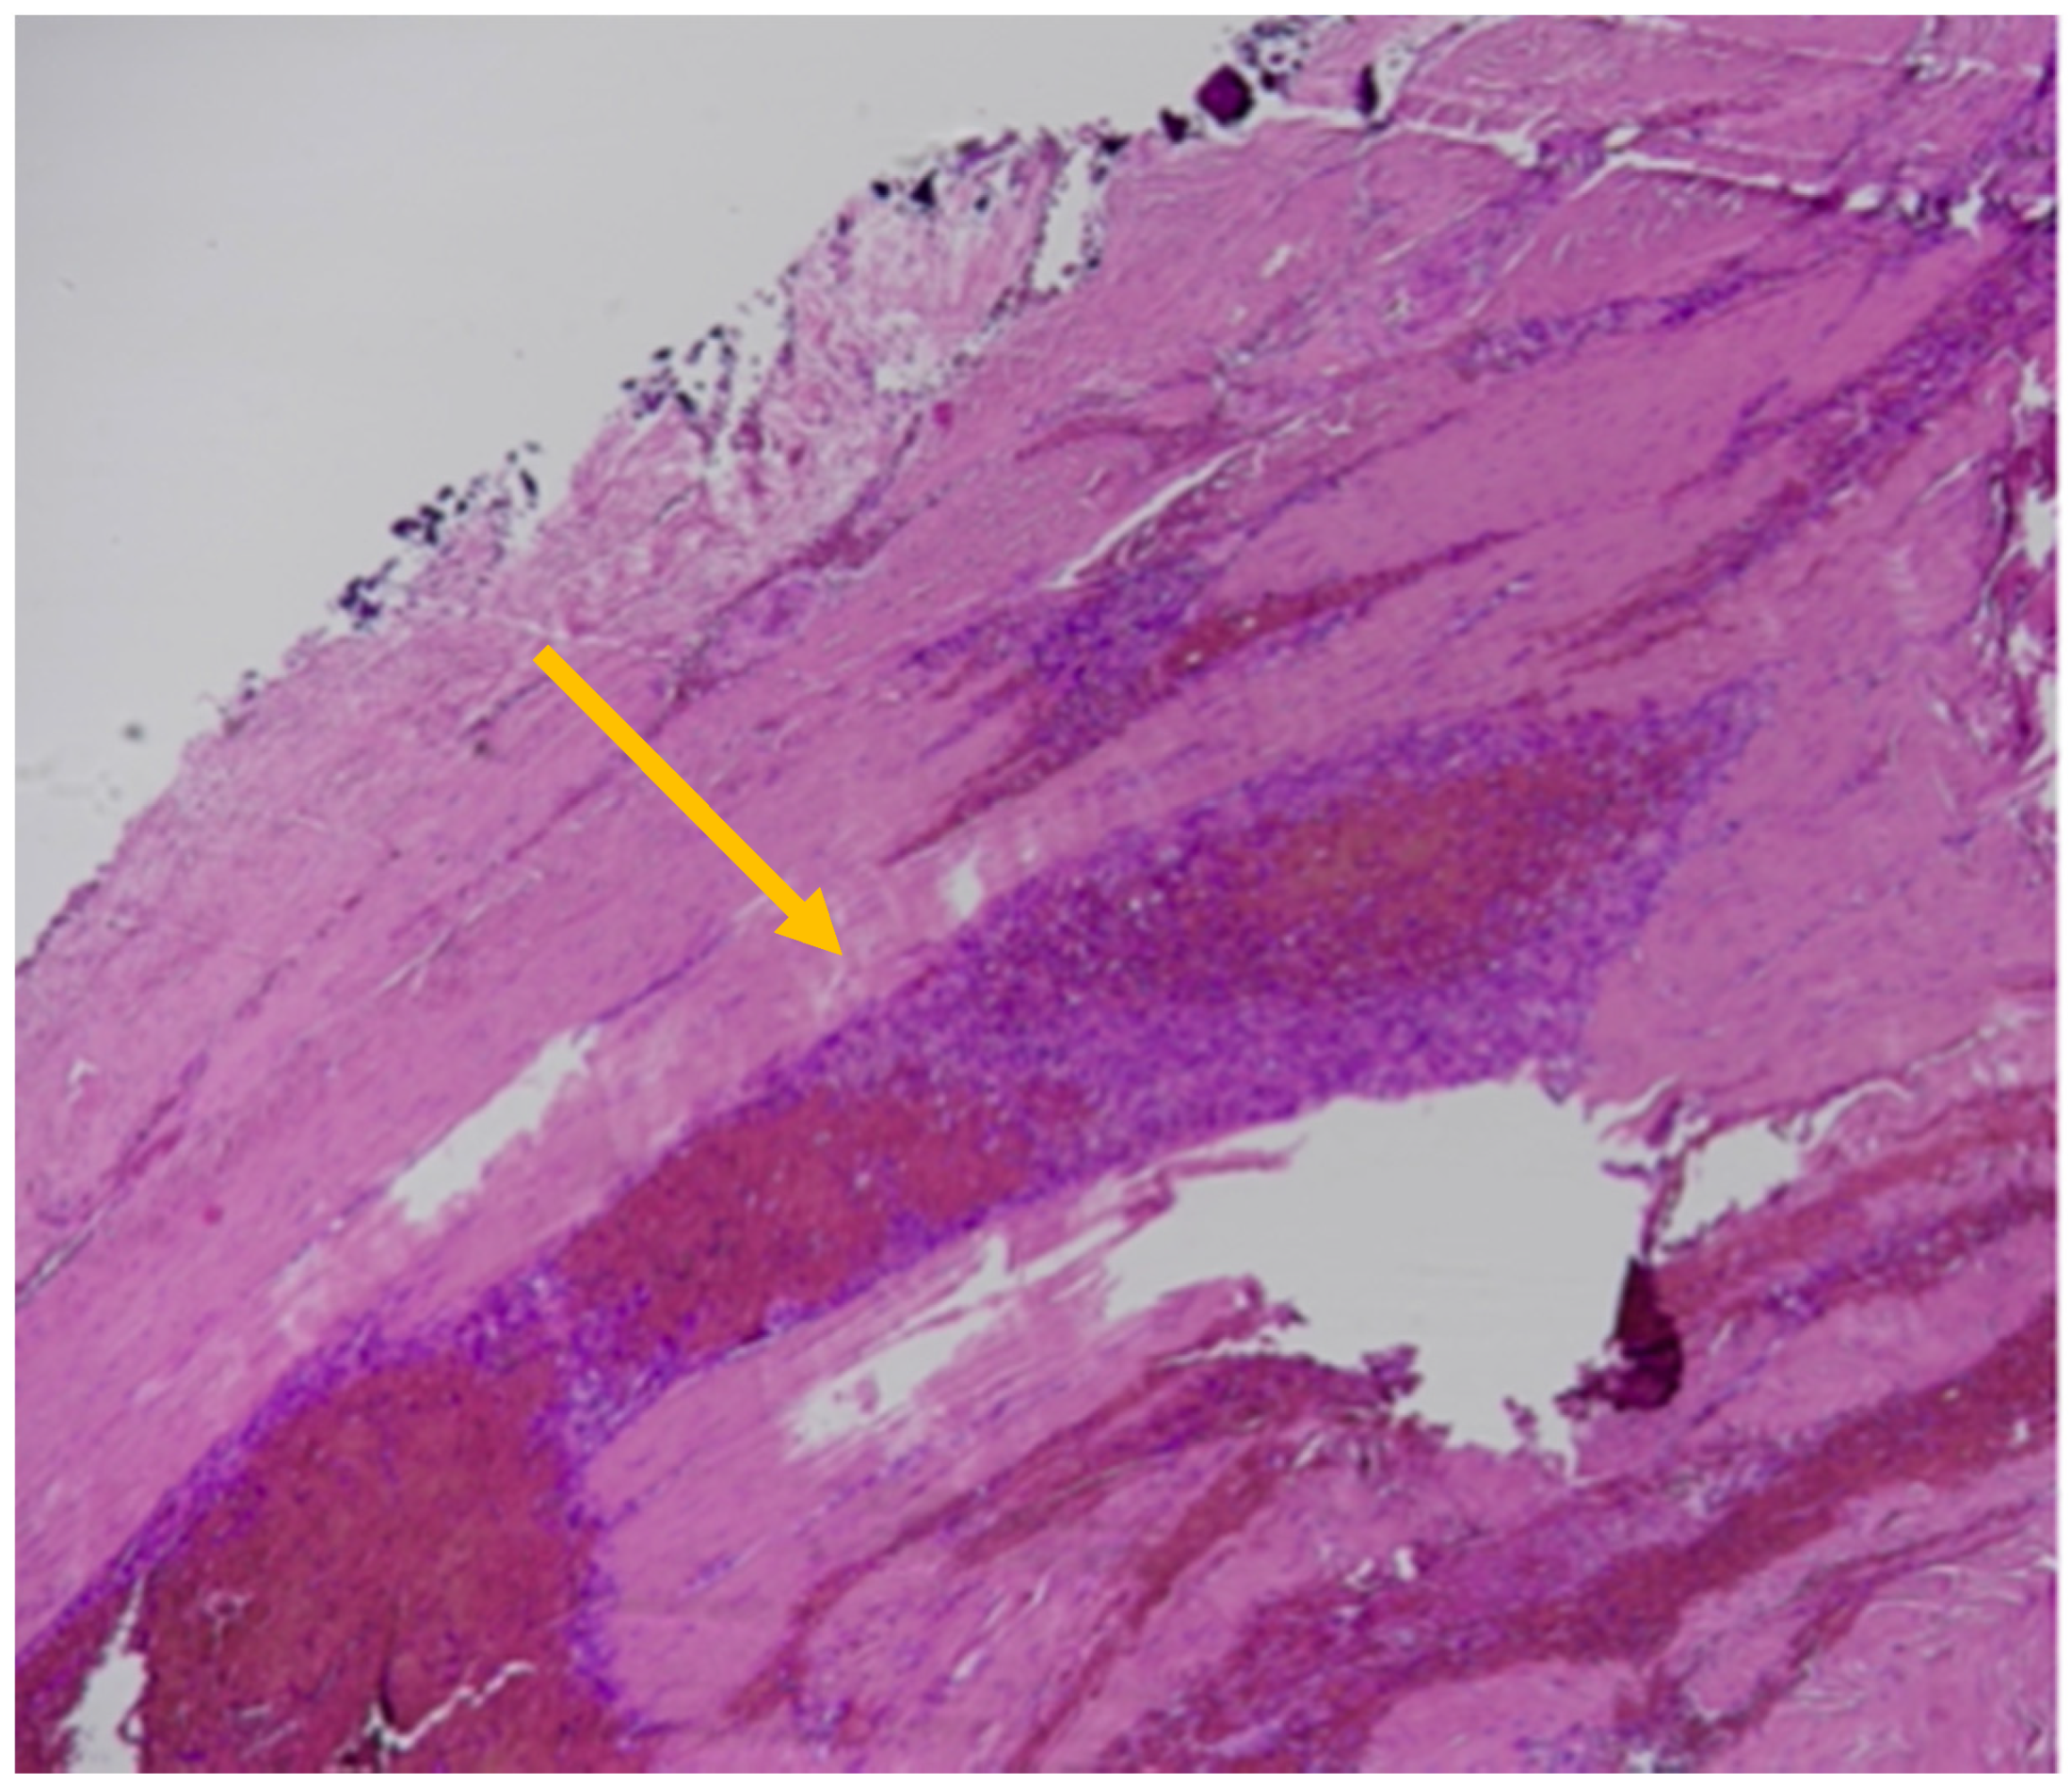

The SDHs showed histological findings consistent with subacute hemorrhages older than 5 days but less than a week, as represented by the formation of granulation tissue with associated breakdown of erythrocytes and some siderophages. A thin layer of fibroblasts was observed between the dura and the clot, and the latter was invaded by new capillary blood vessels [34]. Intense edema was also present based in large pericellular and perivascular empty spaces (Figure 4).

Figure 4.

Histological findings of subacute SDHs > 5 days old: thin layer of fibroblasts between the dura and the clot (yellow arrow); granulation tissue; siderophages; breakdown of erythrocytes (yellow arrow; Hematoxylin & Eosin).